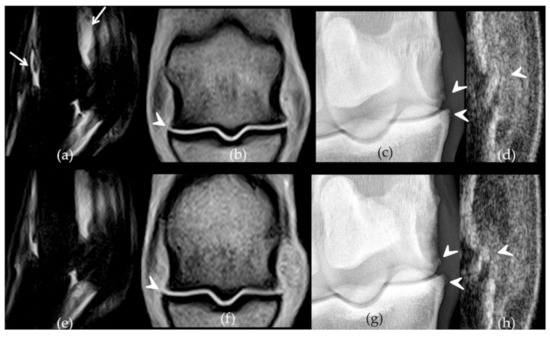

2.2. Follow-Up with Imaging Techniques